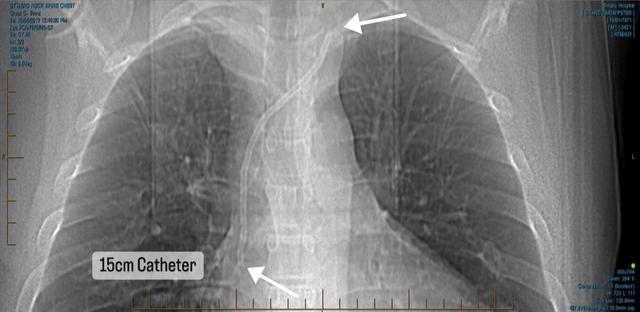

15CM PIECE OF PLASTIC LEFT IN TOP OF HEART – SURGERY NOT AVAILABLE IN NZ

After going through lengthy consultations with cardiologists throughout Australasia, it has been formally confirmed there are no options for removal with no expertise available for this complex treatment injury. The US remains the focal point. Without removal, future dialysis and transplant options are not feasible. We thank everyone for their ongoing support and generosity.

Main image

We are hopeful of finding a surgeon in Melbourne that can apply the same laser sheath removal technique. Going to the US currently is not feasible due to rising costs of surgery and the exchange rate both being cost prohibitive. The average cardiothoracic procedure in Australia is around $70,000 (for an extraction of pacemaker leads), so we are hopeful a surgeon can apply the same principal with an embedded fractured catheter. The major hurdle is the length of time the catheter has remained in situ and the fact they don't do these procedures routinely as it should never happen, hence being in this unique situation. The only way of getting to the US now will be if ACC change their legislation to enable treatment injury cases to get the surgery they need if it's not available in NZ. Thankyou so much to everyone who has donated, we can't reiterate enough how appreciative we are. The attached image is a 3D image created by the surgeon from the US showing the catheter and fragments in bright green sitting in the SVC (superior vena cava) inside the heart.